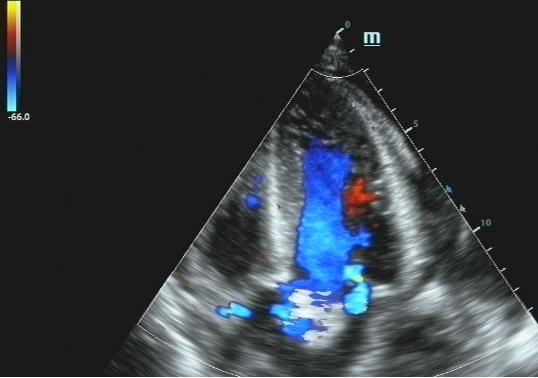

五、彩色多普勒超声:成像技术或兼备彩色能量多普勒功能。

工作原理:用彩色编码技术显示血流影像。设定流向探头的血流为红色,背离探头的血流为蓝色,湍流为绿色。颜色的辉度与速度成正比。

彩超logiq怎么读B超、彩超“傻傻分不清楚”?其实区别就在这!_https://www.jmylbn.com_新闻资讯_第9张

应用范围:彩色多普勒成像系统所显示的最大血流速度的彩色图像十分清晰,与M型、二维超声和频谱多普勒超声结合,可获可靠的诊断信息。